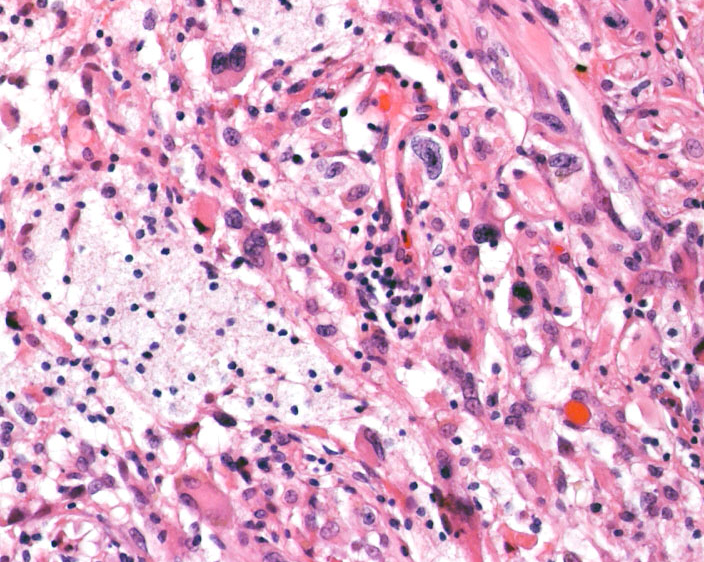

星細胞 astrocytesが強い多型性 pleomorphism を示すのでこの名があります

グリオーマの場合は核多型性というのは悪性ということと同義になることが多いのですが,この腫瘍の場合はそうではありません,著しい核の多型性のために,悪性腫瘍とくに退形成性星細胞腫や膠芽腫と誤診しないことが重要です,脂肪滴を含むlipitized cells(黄色の矢印)が混在 することもあります(xanthomatous change)

reticulin fiberに囲まれeosinophilic granular bodiesを含む特徴的な組織像を示します。時に神経細胞由来の腫瘍細胞を含みます (neuronal differentiation)

多単核細胞の核異型から多核の巨細胞まで見られますが,分裂像はなくMIB-1 indexは低いのが特徴です

lipidized cells (胞体に空胞が見られるastrocyte), pleomorphic / polynuclear astrocytes, perivascular lymphocyte infiltration, macrophageの集簇などがみられます。著明なmacrophageの浸潤があります。lipidized cellsが見られない場合にはanaplastic astrocytomaとの鑑別がHE染色のみでは難しいと考えて下さい。MIB-1は1%でした。